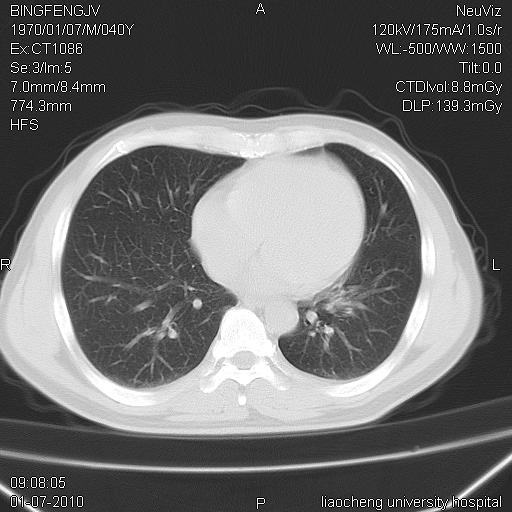

标题: CT23764B:男 40 肺部CT [打印本页]

标题: CT23764B:男 40 肺部CT

治疗2周后

炎症性病灶,继发性改变。

考虑左肺上叶近胸膜下炎症并肺气囊形成。

炎症,大部吸收。